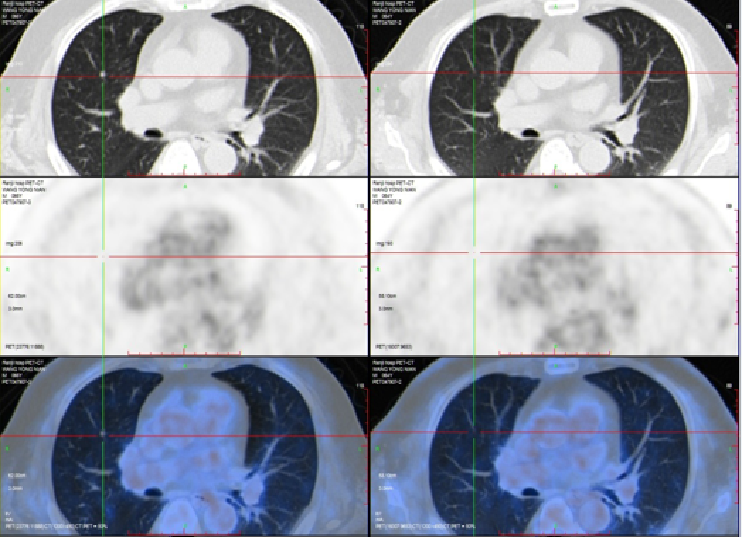

2020-3-6 胸部CT:两肺多发小斑点灶及微小结节,直径约3-10mm,较前(2019-11-05)部分增大。评估病情PD。

【TAS-102+呋喹替尼】2021-6-11 上腹部MRI提示“直肠CA根治术+肝转移瘤切除术+胆囊切除术”后改变,肝右叶肿瘤介入术后,肝右叶部分病灶较前(2020-12-2)范围缩小,部分病灶较前为新增,肝门区及后腹膜处多发肿大淋巴结,肝右叶见结节、斑片灶,较大者直径约35mm;胸部CT提示右肺上叶斜裂胸膜下结节,较前(2021-2-10)病灶内小空泡消失。两肺多发小斑点灶及小结节,较前部分有所减小,期间有肿瘤标志物进行性升高。

2021-12-7 胸部CT:右肺上叶斜裂胸膜下结节,较前缩小。